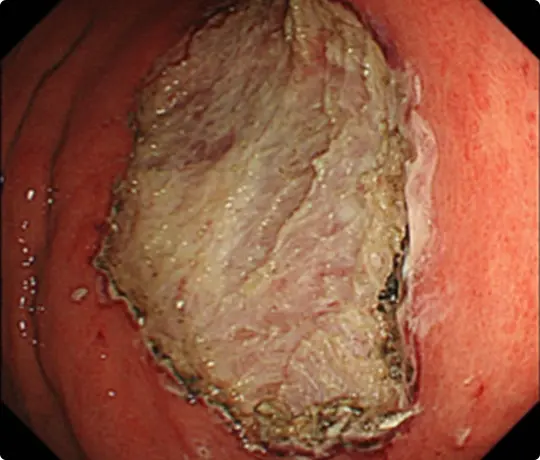

約25mmの十二指腸腫瘍を認めます。

病変の範囲を診断し、周りに電気メスでマークを付けます。

粘膜の下に液体を注入して病変を浮かせます。

マークの外側の粘膜を電気メスで切開。

粘膜の下の組織(粘膜下層)を電気メスで剥がしているところです。

十二指腸の粘膜下層は非常に薄く筋層を損傷し穿孔するリスクが高いとされています。

Underwater ESD(生理食塩水の中で行うESD)を行うことで光の反射がなくなり、拡大効果もあるため、精密に剥離することが可能になります。

穿孔(壁に穴があくこと)などの問題なく、病変を切除しました。

切除後は潰瘍が出来ますが、1~2ヵ月で治ります。十二指腸ESD後は、遅発性穿孔予防のため、クリップなどで治療後の潰瘍を完全に閉じるようにしています。